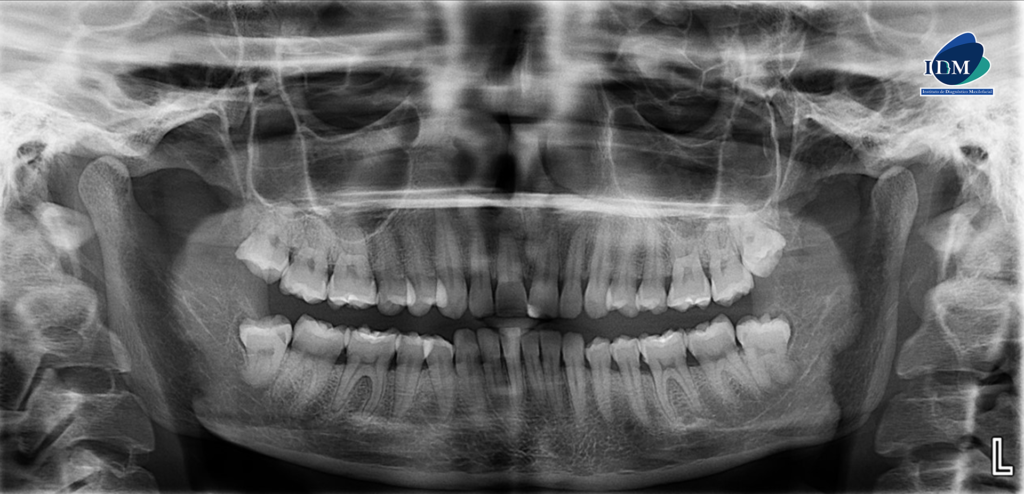

En la radiografía panorámica (Figura 1), se observa pieza 33 con pérdida del lumen del conducto radicular a nivel del tercio medio y apical.

Radiografia Panorámica